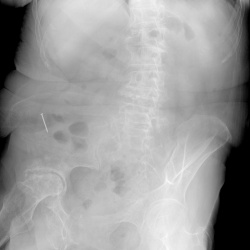

Пациентка 78 лет. Поступила в больницу в тяжелом состоянии, при выполнении снимка лёгких рентгенолаборант обратила внимание, что в проекции брюшной полости инородное тело металлической...